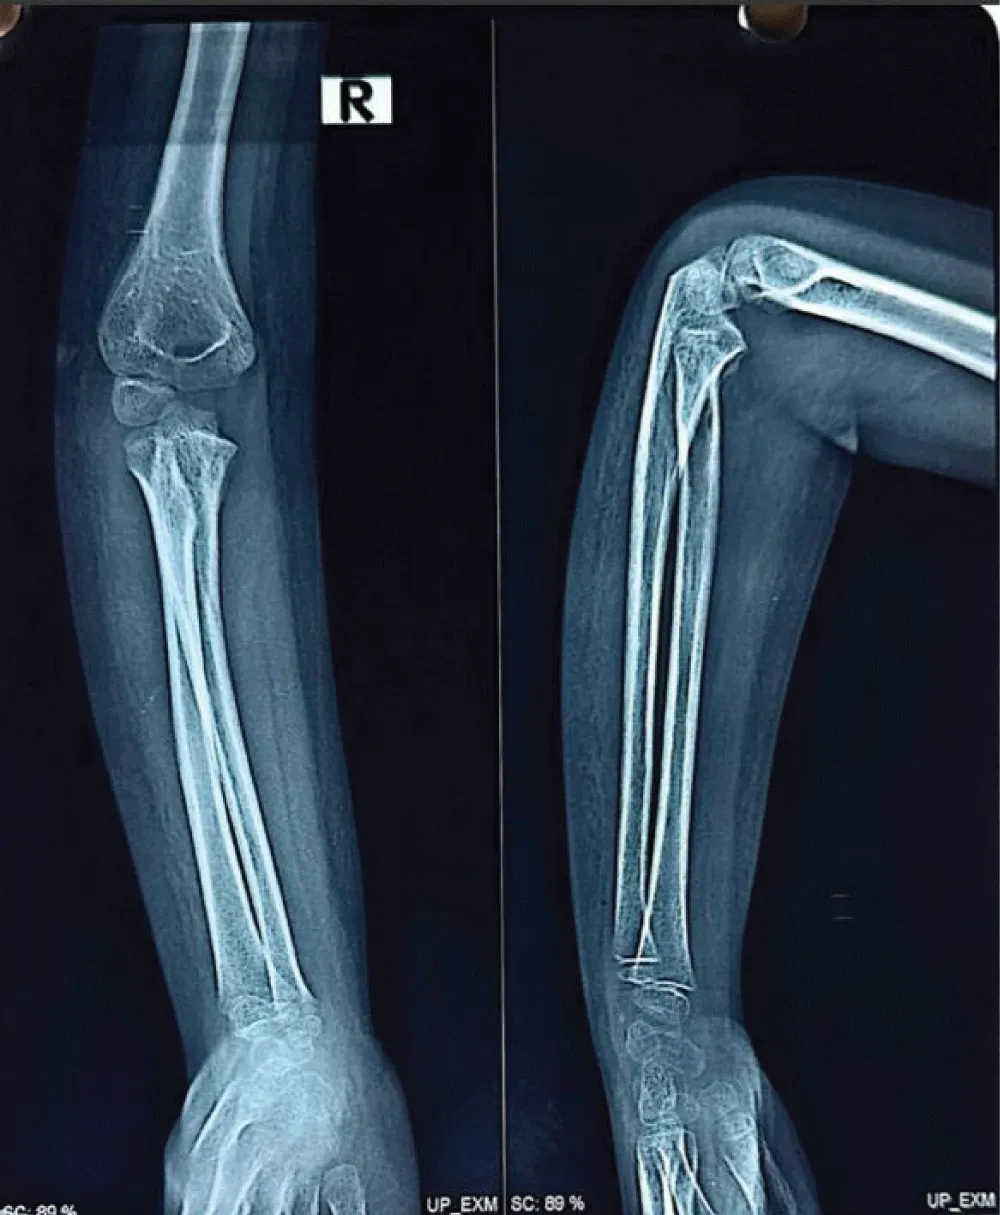

Radiograph of the elbow joint revealed a well-defined calcified mass parallel to the humerus, with a convex shape extending along the supracondylar region with the classical features of heterotopic ossification. The patient guardians declined further advanced imaging studies, including MRI, citing personal reasons. Consequently, the diagnosis of Myositis Ossificans Traumatica was made based exclusively on radiographic findings.

Radiological imaging showed residual heterotopic ossification along the humerus, indicating incomplete resolution. Multiple radiographs of the right upper limb-including the arm, forearm, and elbow joint were taken during outpatient visits at the patient’s convenience and were compared over time to monitor progress (figure 7,8). A well-visualized radiograph obtained 10 months after the initial injury showed near-complete resolution of the heterotopic ossification (Figure 9).